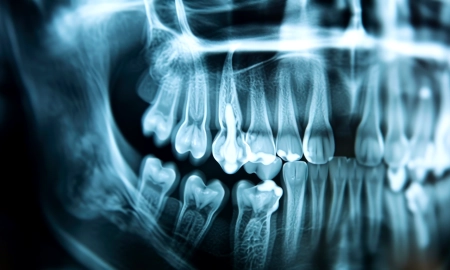

Radiographies dentaires

Les radiographies dentaires permettent de visualiser les structures internes de la bouche. Elles aident à détecter la perte osseuse autour des dents, un signe avancé de maladie parodontale. Les radiographies complètent l’examen clinique en fournissant des informations détaillées sur l’état des os de soutien.

Analyse des radiographies

Les radiographies révèlent la quantité de perte osseuse autour des dents. Une perte osseuse significative est un signe avancé de maladie parodontale. Elle nécessite un traitement immédiat pour éviter la perte de dents.

- Des examens complémentaires tels que radiographies et examens microbiologiques (totalement indolores) ;